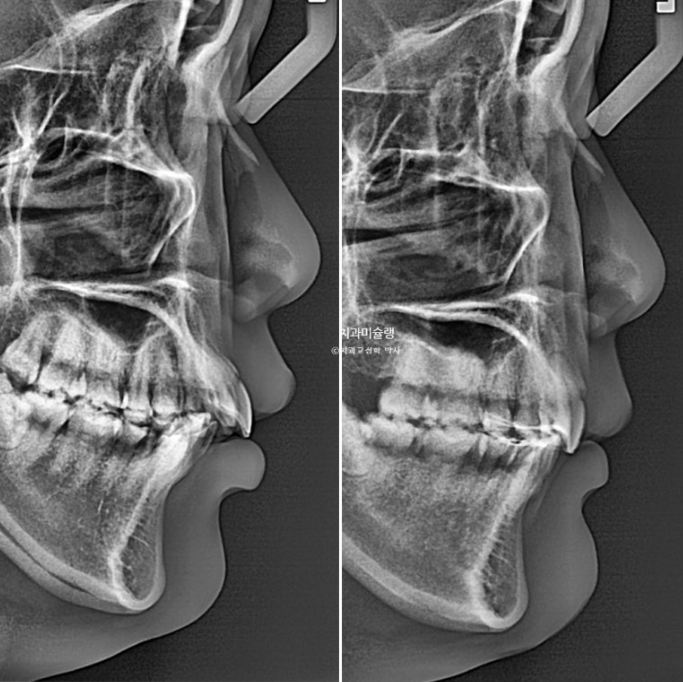

골격분석 결과 심한 상악골 전방 돌출을 동반한 골격성 2급 부정교합 입니다.

상악골 과잉에 의한 돌출은 돌출입 교정 중에서도 난이도가 높습니다.

상악과 하악의 골격 부조화가 심해 아래턱이 상대적으로 뒤로 밀려있는 상태여서 위 앞니 각도를 이상적으로 유지하기가 쉽지 않습니다.

앞니 각도는 적절하며

2022.11~2026.01

상악골 과잉이 심한 골격에서 교정으로 위턱뼈가 들어가는 것은 아니지만 최소한 위 앞니는 교정으로 예쁘게 넣어줄 수 있습니다.

3년에 걸친 치료기간 동안 치근흡수는 없고 치근평행도는 양호합니다.

발치교정에서 전후 파놓라마 엑스레이를 반드시 첨부하는 이유는

인비절라인으로 뿌리이동은 안된다 라는 잘못된 정보를 듣고 오는 환자분들을 안심시켜 드리기 위함입니다.

아래 앞니는 계획대로 뒤로 1mm도 뒤로 들어감 없이 잘 유지가 되었고 위 앞니는 치조골이 허용하는 범위 내에서 아래앞니와 만나기 위해 최대한 뒤로 들어갔습니다.